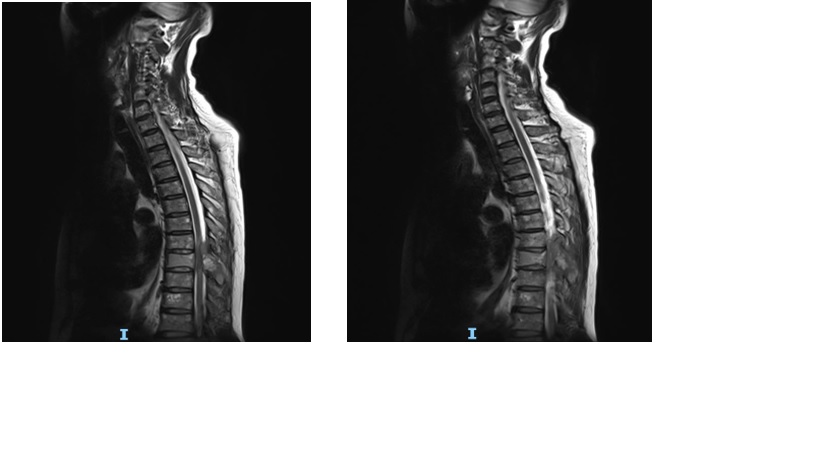

MRI cột sống ngực

Hình 2

Kết quả MRI cột sống ngực có gadolium:

Thâm nhiễm tủy xương đốt sống ngực T8 lan ra mô mềm xung quanh và vào ống sống chèn ép tủy

Chẩn đoán xác định: chèn ép tủy sống ngực T8